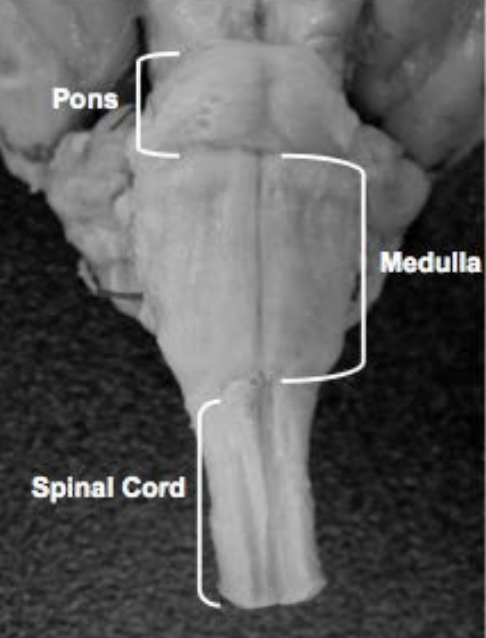

Pons

A

Medulla

Spinal cord

Voluntary movement, pain, sensation